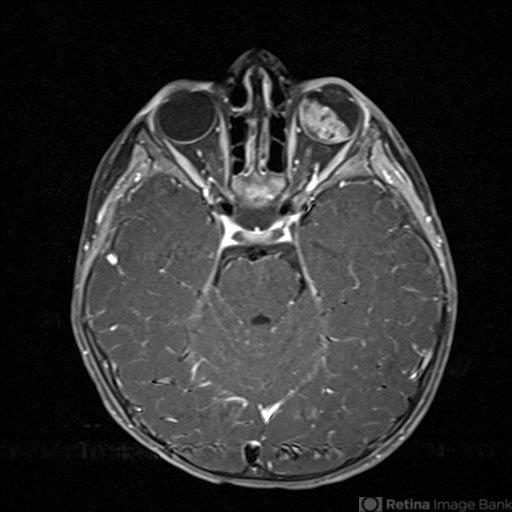

- MRI used to evaluate a child with retinoblastoma. Note the white tumor on the T1 weighted image. There is no evidence of extrascleral or intramural invasion nor PNET.